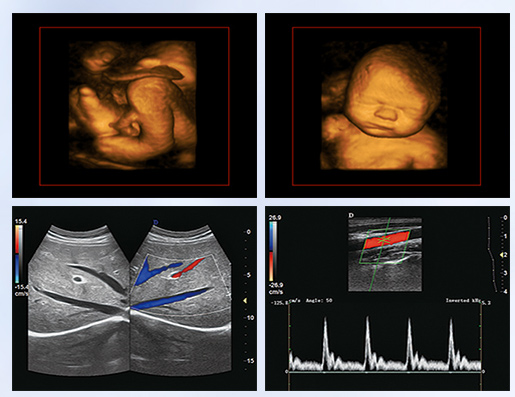

超聲學科的發(fā)展史,猶如一卷悠遠綿長的畫冊。從黑白B超機到彩超機,從一維、二維向三維立體動態(tài),從推車式B超機到便攜式彩超機,從觀察人體解剖學到分析人體組織內細微結構和功能。隨著科學技術的不斷發(fā)展,B超機功能也越來越方便強大。

超聲作為一門醫(yī)、理、工相結合的學科,涵蓋超聲診斷、超聲治療和超聲工程技術等門類,其在臨床診斷和治療中發(fā)揮著日益重要的作用。B超機借助各種超聲探頭,以精湛的技術和嚴謹的態(tài)度掃描著人體臟器內的細微病變,給臨床提供準確而快捷的檢查報告,在影影綽綽間,發(fā)現病魔的蛛絲馬跡中,用“金睛火眼”挽救患者性命……超聲的每一幅圖像,都是靠超聲醫(yī)生親自探查并采集的,每一個患者,至少都有10張以上的圖像存儲,對于比較復雜的病例,有幾十甚至上百張。而且所有的圖像,都需要超聲醫(yī)生在邊探查的時候,邊思考分析。這,是一個真正手腦并用的工作。